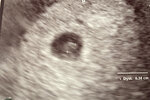

Witam się nieśmiało. U mnie końcówka 6 -tego tygodnia.

Załączniki

• AD003638-74D2-4FFD-AF84-F04169F71275.jpeg

AD003638-74D2-4FFD-AF84-F04169F71275.jpeg

99,6 KB · Wyświetleń: 99